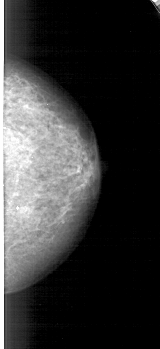

A_1723_1.RIGHT_CC

RIGHT_CC LINES 4531 PIXELS_PER_LINE 2071 BITS_PER_PIXEL 12 RESOLUTION 43.5 NON_OVERLAY